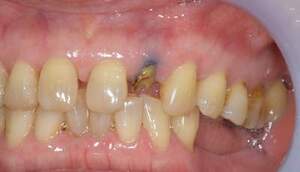

MTM開始直後と、終了後です。フックの位置が変わっているのがわかると思いますが、それが歯が動いた証拠となります。

MTM中。頬側には審美面の回復のために仮歯がついています。

歯からはフック、隣り合った歯にはワイヤーが渡してあります。そこにゴムをひっかけて歯を挺出させます。